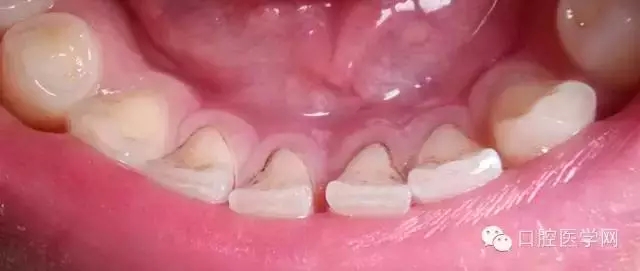

另一種則是牙齒出現(xiàn)了或深或淺的齲壞,從外面看就表現(xiàn)為一個(gè)黑點(diǎn),通常位于窩溝點(diǎn)隙(牙面上點(diǎn)狀或線狀凹陷)。齲齒的罪魁禍?zhǔn)资强谇恢械哪承┘?xì)菌,但它們破壞牙齒也是需要時(shí)間的,從初期的變色到最終形成齲洞,通常需要1年半到兩年。在此期間,我們多留心自己的牙齒,完全可能把齲壞扼殺在萌芽階段。如何才能及時(shí)發(fā)現(xiàn)這種隱匿的蛀牙呢?找位好牙醫(yī),半年檢查牙齒!

一旦確認(rèn)牙齒上的小黑點(diǎn)是齲齒就應(yīng)該盡早修補(bǔ),以阻止病變的發(fā)展。如果任由其繼續(xù)發(fā)展就會(huì)變成明顯的齲洞,這時(shí)患者會(huì)對(duì)冷熱酸甜等食物刺激敏感;當(dāng)損傷進(jìn)一步到達(dá)牙髓(即老百姓說的“牙神經(jīng)”),就會(huì)疼痛難忍,嚴(yán)重影響日常生活。臨床上見到很多人都會(huì)等到牙痛得受不了,才到醫(yī)院就診。這時(shí)通常不能靠單純補(bǔ)牙來解決問題,可能還要做根管治療甚至拔除患牙、進(jìn)行假牙修復(fù),費(fèi)時(shí)費(fèi)力又費(fèi)錢,人還遭罪,可謂“小洞不補(bǔ),大洞吃苦”。